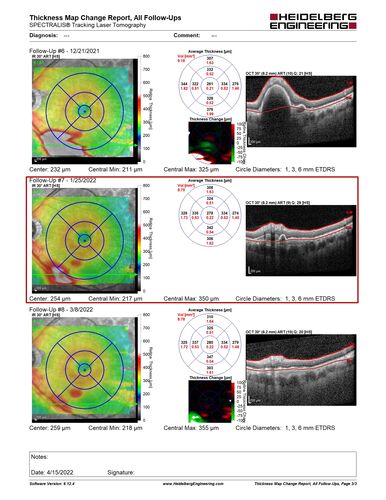

Massive subretinal hemorrhage right eye - polypoidal choroidal vasculopathy

Patient had sudden vision loss right eye. Had vitrectomy. The left eye had IPCV not responsive to avastin but he did respond to PDT. See album notes for more detail.

ipcv5_MAPS_03.JPG

Massive Subretinal Hemorrhage Polypoidal Choroidal Vasculopathy